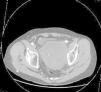

Presentamos el caso de un paciente de 71 años diagnosticado hace 2 años de aneurisma de aorta abdominal y aneurisma de arteria hipogástrica izquierda trombosado, realizando bypass aorto-aórtico y ligadura y exclusión del segundo. Un año más tarde, tras dolor en fosa ilíaca izquierda se descubre endofuga del aneurisma hipogástrico realizando cierre y embolización del saco mediante radiología intervencionista (coils y pegamento biológico), procedimiento que fue necesario repetir 8 meses después por el mismo motivo. Tres meses después, consulta en el servicio de urgencia, esta vez por clínica de estreñimiento, sin dificultad para eliminar gases por el ano y oliguria de 3 semanas de evolución, sin otra sintomatología. Al tacto rectal se palpa masa pélvica que comprime ampolla rectal en su cara anterior e izquierda, no pulsátil, sugiriendo compresión extrínseca, sin productos patológicos. En la radiografía de abdomen se aprecia leve dilatación de escasas asas de intestino delgado y colon hasta descendente. Se realiza ecografía y angio-TC describiéndose masa pélvica compatible con gran aneurisma trombosado de la arteria hipogástrica izquierda relleno de coils, que comprime recto y vejiga e hidronefrosis izquierda leve (fig. 1). Se interviene de forma programada, a través de incisión abdominal, retrayendo el peritoneo hasta alcanzar el retroperitoneo. Se realizó aneurismotomía con extracción y limpieza del contenido, así como sutura de un punto sangrante en el saco aneurismático (fig. 2). En el primer día postoperatorio, el paciente es reintervenido por sangrado en músculo psoas, realizando hemostasia. También se diagnostica tromboembolismo pulmonar que obliga a la colocación de un filtro temporal en la vena cava y anticoagulación con heparinas de bajo peso molecular. Posteriormente evoluciona favorablemente, siendo dado de alta.